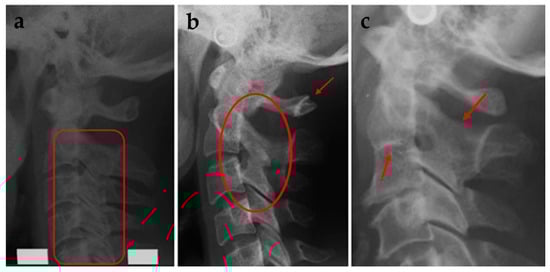

For the assessment of morphological deviations in the upper spine, a visual analysis has been conducted of the first 5 cervical vertebrae. The deviations are classified in two groups, fusions (FUS) or posterior arch deficiencies (PAD), according to Sandham [25]. FUS was classified as fusion, block fusion, or occipitalisation [25] and PAD was classified as partial cleft or dehiscence of the cervical vertebrae (Figure 6). All the assessments were checked by LS, who is experienced in assessment of the upper spine.

Figure 6.

(a) Block fusion between C2-C3-C4-C5. (b) Fusion between C2-C3 and partial cleft of C1. (c) Fusion between corpus and arcus of C2-C3 [25].